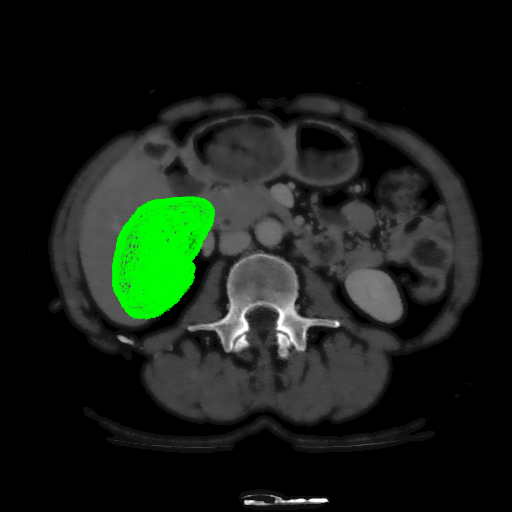

For MSER tracking, Donoser and Bischof [5] presented three different applications; license plate tracking, face tracking and the segmentation of a fiber network. In the third application, a fiber network is reconstructed in 3D by tracking a slice of the data along the axis orthogonal to the image data. Analogously, we track organs in slices of a Computed Tomography (CT) scan, to generate a 3D segmentation. We use the CT data provided in the 3DIRCADb dataset222The dataset is available on http://ircad.fr/research/3d-ircadb-01 [14].

To initialize the tracking process, the organ is segmented in an arbitrary slice of the CT data by a bounding box. The most stable MSHR is then selected in the initialization process for tracking. The respective MSHR is tracked through the slice data along the axis orthogonal to the image data. An example of the tracked regions is visualized for two examples in Fig. 7. Given the segmentations of the single slices, the organ can be reconstructed in 3D. We compare the reconstruction for MSER and MSHR tracking in Fig. 8. To enhance the visualization, the datapoints are triangulated and the surface normals calculated. Since the contrast of the organs can be very low in CT images, the MSER tracking has difficulties catching the organ boundaries. Furthermore, the organ is sometimes partely lighter and darker than the background, which may lead to MSER tracking failure. The proposed MSHR tracking copes well with these difficulties, and the reconstructions are significantly better.

Figure 7: Two examples sequences from the 3DIRCADb dataset [14]. Given an initial selection of a single slice (the middle image in (a) and (b)) of the organ, the proposed MSHR tracking tracks the region forward and backwards in space. The segmented slices can be used to reconstruct the organ, see Fig. 8 for an example reconstruction.